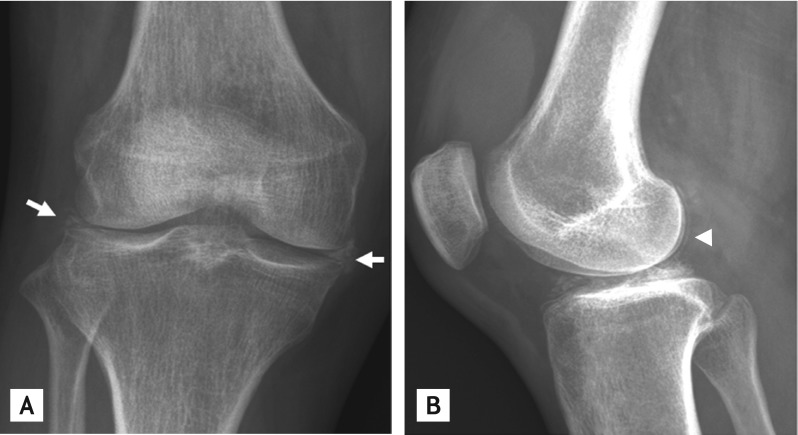

A 52-year-old woman presented with painful swelling in both knees for 7 days. Physical examination identified marked swelling and tenderness in both knee joints that she reported to have recurred for the past 6 years. Laboratory tests determined the erythrocyte sedimentation rate to be 107 mm/hr, C-reactive protein as 25.55 mg/dL, and serum uric acid levels as 4.1 mg/dL. Calcium pyrophosphate dihydrate (CPPD) crystals were found on polarized light microscopy examination of knee joint synovial fluid. Cultures identified no microorganisms. Plain radiography of the right knee revealed multiple calcifications in the medial and lateral menisci and the femoral condylar cartilage (Fig. 1). Dual-energy computed tomography (DECT), which differentiates monosodium urate (color-coded in green) from calcium (color-coded in blue), revealed multiple calcium depositions in the anterior and posterior cruciate ligaments, as well as in both menisci and the femoral condylar cartilage (Fig. 2). The patient was diagnosed as having CPPD crystal deposition disease of both knee joints. Intra-articular injection of triamcinolone effectively relieved her pain.

In gouty arthritis, DECT is a useful noninvasive and inexpensive imaging modality for detecting urate deposits, especially when the acquisition of synovial fluid tophi is not possible and both septic arthritis and CPPD crystal deposition disease are possible diagnoses. DECT is also useful for detecting coronary calcium deposition and urinary calculi. Although calcification is often easily recognized on plain radiographs, DECT is a useful tool when crystal examination is not available or radiography is not easily interpretable.